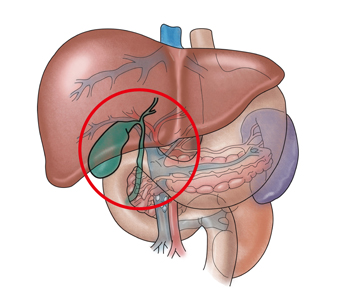

만성 담낭염은 담낭의 만성적인 염증 질환을 말하며 대부분 담석증 때문에 발생하게 됩니다.

만성 담낭염은 담석이 담낭을 지속적으로 자극하여 급성 또는 아급성의 담낭염이 반복됨으로써 발생합니다. 담석으로 인해 담낭 내벽의 점막이 손상되고, 반복적인 염증 때문에 림프구의 침윤과 섬유화가 진행됩니다. 이로 인해 담낭벽이 두꺼워지고 석회질의 침착이 생기기도 합니다.